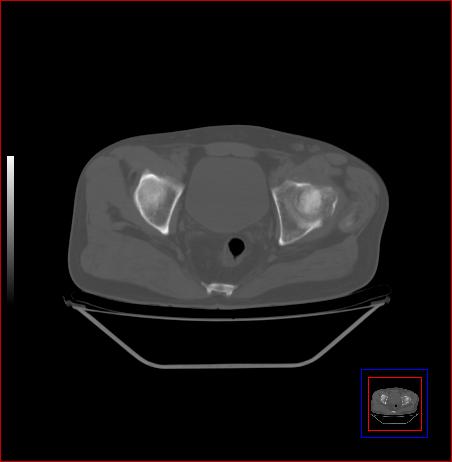

标题: CT15143:髋关节结核?

男,49,髋关节疼痛1年,无肺结核。

支持左侧髋关节结核合并轻度半脱位

骨质破坏,硬化,周围软组织脓肿,支持骨结核

骨质破坏,硬化,周围软组织脓肿,关节间隙增宽,支持骨结核

骨质破坏,硬化,周围软组织脓肿,关节间隙增宽,支持骨结核 .应与无菌坏死鉴别

支持:左侧髋关节结核合并轻度半脱位!

可以是结核,也可以是无菌坏死,还可以是先天髋关节脱位,不结合临床病史,只凭图像鉴别,请各位老师指教。

支持 左侧髋关节结核并半脱位。